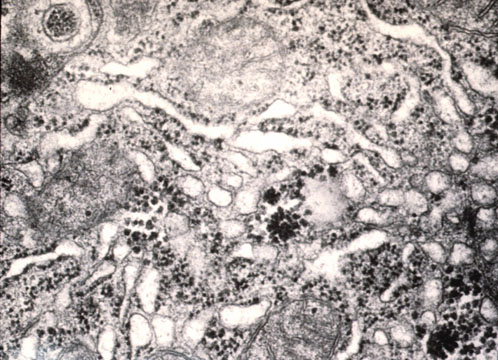

Lysosomes

Fig 23 - LYSOSOMES: Located near the bile canaliculus.They sequester toxic metals(iron,copper) and degrade old organelles.